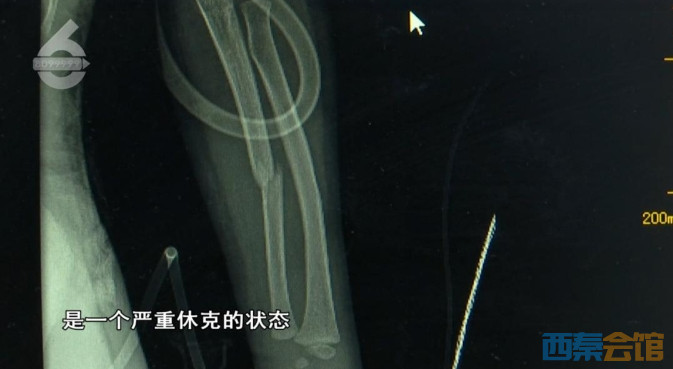

昆明市儿童医院SICU医生谢超介绍,女童坠落过程中被树隔挡了一下,没有造成严重的颅脑损伤,但情况非常危急,四肢有骨折,脑部有挫裂伤,肺挫伤、出血,气胸,膈肌损伤,脾胃破裂,已出现严重的休克状态。谢超表示,最幸运的是,孩子没有直接直接摔到头部,不然后果不堪设想。